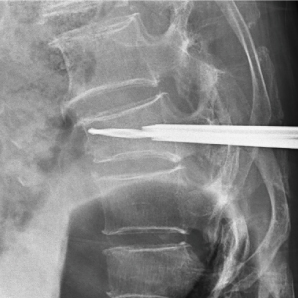

Le Compax 500 (Pro) est livré avec la dernière technologie numérique de toute la chaîne d'imagerie, améliorant de manière approfondie la qualité des images peropératoires en orthopédie et fournissant des détails d'image plus riches pour le diagnostic clinique. Le produit est équipé d'un détecteur de panel plat dynamique de grande taille, avec des images claires et délicates qui répondent à une variété d'examens cliniques. La grande géométrie du bras C et divers conceptions humanisées peuvent facilement répondre aux besoins chirurgicaux des patients de toutes tailles, fournissant des solutions d'imagerie plus précises, plus intelligentes et plus efficaces pour le diagnostic et le traitement des maladies cliniques telles que l'orthopédie, la chirurgie vertébrale et les procédures de gestion de la douleur.

Traitement d'image avancé

• Correction métallique

Pour réduire les artefacts métalliques et prévenir le rayonnement sur-dose.

• Amélioration des bords

Pour les détails osseux exquis et la délimitation claire des tissus mous.